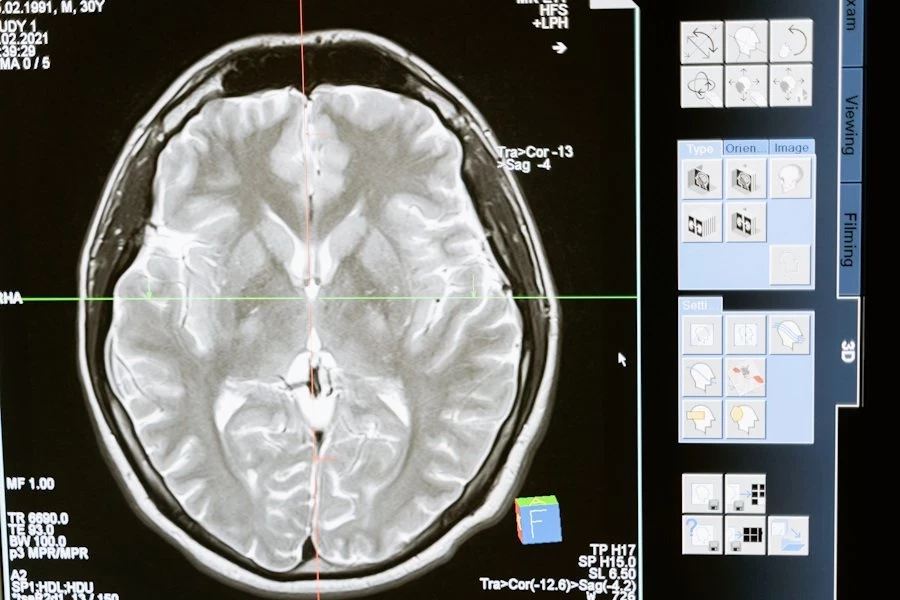

Зрительная рабочая память — это система мозга, которая помогает нам временно удерживать важные визуальные детали, например, при чтении, решении головоломок или сравнении объектов. Исследователи опирались на тета-гамма-модель, которая связывает объем рабочей памяти с частотой тета-колебаний мозга. Эти ритмичные волны появляются в переходе от бодрствования к расслаблению.

В эксперименте испанские ученые использовали метод нейронного синхронизирования: участникам показывали ритмичные визуальные мерцания и проигрывали звуковые сигналы. Затем проводился тест: испытуемые запоминали цвета квадратов на экране и указывали, изменился ли какой-либо из них в новом наборе.

Результаты впечатляют: стимуляция тета-ритмов мозга как в ускоренном, так и в замедленном темпе улучшила рабочую память у всех участников. Особенно это проявилось у тех, чьи результаты в контрольных условиях были ниже среднего.